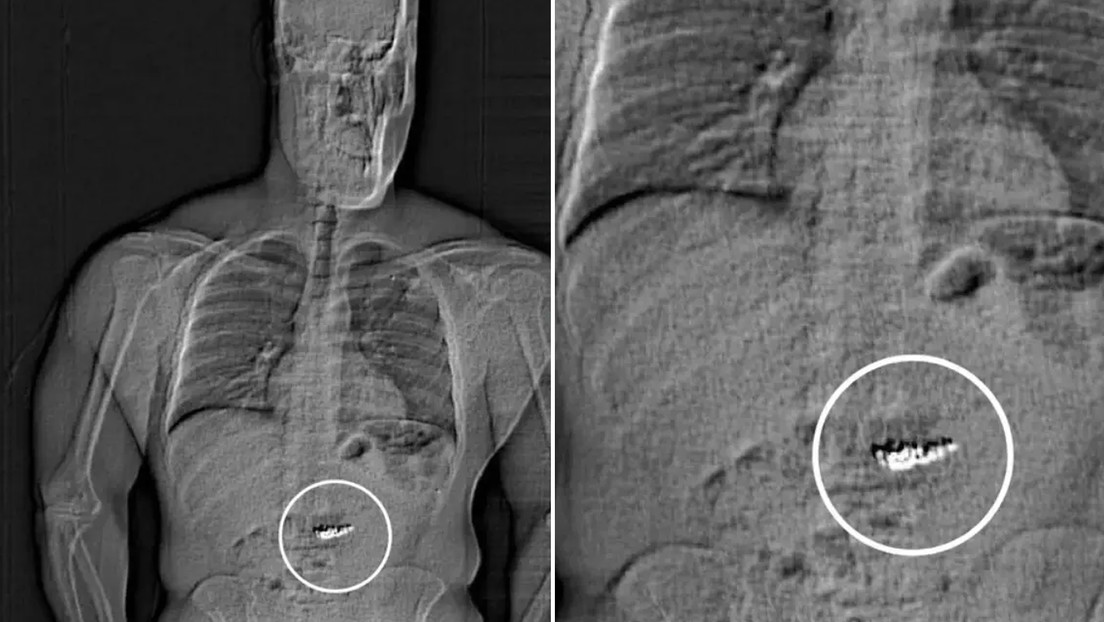

Tras escanear su cuerpo, los detectives encontraron objetos extraños recorriendo su tracto digestivo y determinaron que eran las joyas. Actualmente se enfrenta a cargos de hurto mayor en primer grado y robo con el rostro cubierto.